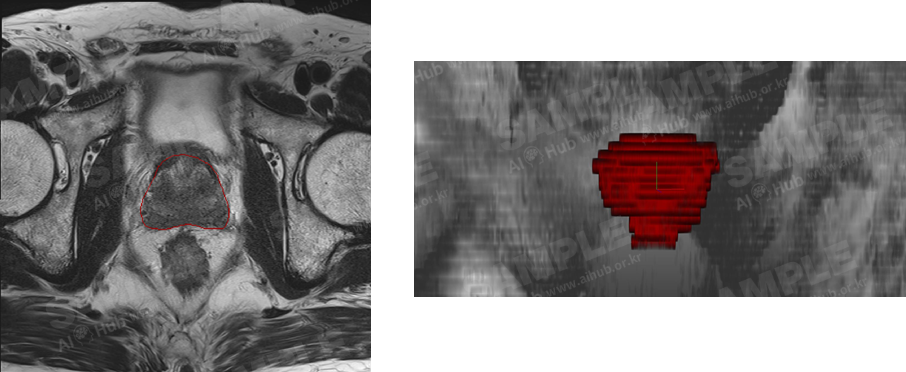

대표도면

<그림2. 전립선암 환자 MRI 영상과 전립선 영역 레이블링 결과 (우측 빠간영역) 예시>